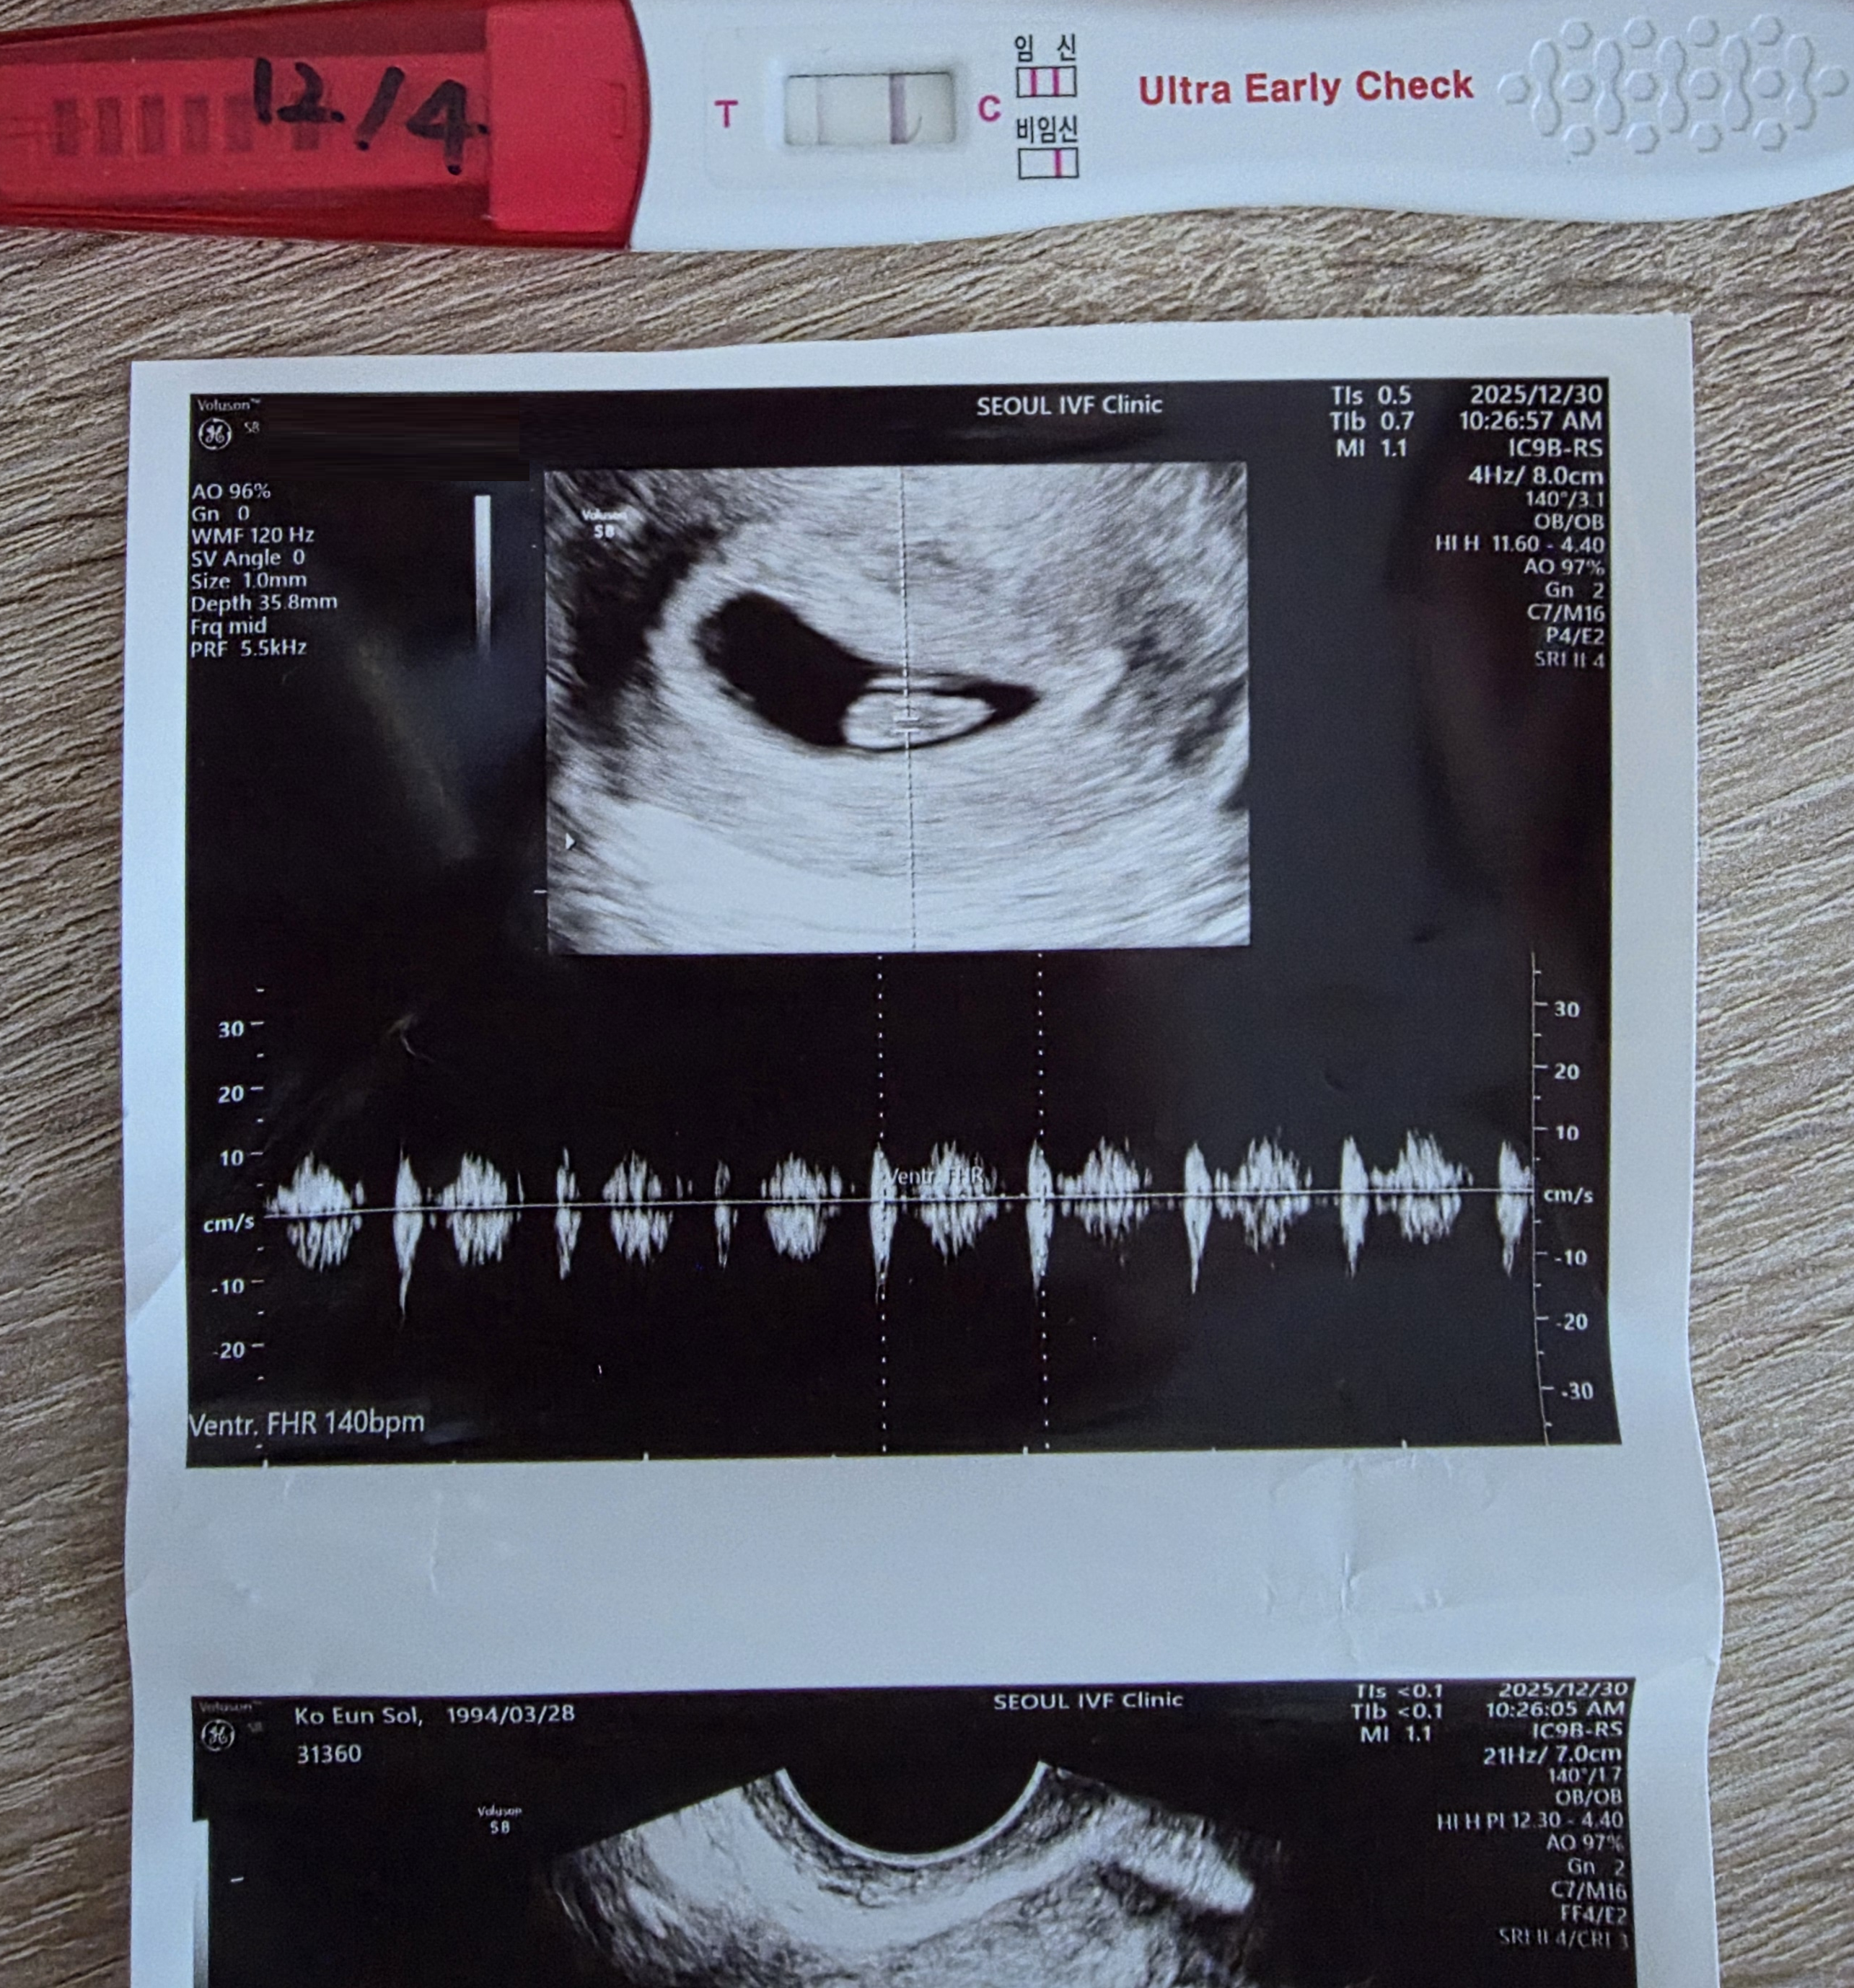

| 가슴 떨리는 임신 이야기를 공유해 주세요. | 이전에 세 번의 임신과 유산을 경험했기에, 시험관으로 다시 임신 소식을 들었을 때도 기쁨보다 걱정이 먼저 앞섰습니다. 쉽게 안도할 수 없었고, 온전히 기뻐하기에는 마음이 조심스러웠습니다. 하지만 주차가 지날수록 아기가 쑥쑥 자라는 모습을 확인하며 점점 기쁨과 행복이 커져 갔습니다. |

| 치료 도중 느꼈던 가장 기뻤던 순간과 절망적인 것들은 무엇인가요? 잊지 못할 경험이 있나요? | 가장 기뻤던 순간은 초음파로 아기의 성장을 확인하고 심장소리를 들을 때마다였습니다. 건강하게 자라는 모습을 눈으로 확인할 때 느끼는 안도감과 행복은 말로 다 표현할 수 없었습니다. 반면 가장 절망적이었던 순간은 임신 6주 차 즈음 출혈이 있었을 때입니다. 천진난만하게 아바타 영화를 보러 가던 길 배고파서 서브웨이 주문을 하고 있는데 쎄한 느낌이 들어서 화장실로 달려갔어요. 꿀렁하고 피가 나오는데 순간 마음이 철렁해서 남편에게 전화하고 급히 병원을 향했습니다. 가는 길에도 출혈이 상당해서 아가가 잘못된 것 같다는 느낌에 병원으로 향하는 그 길 위에서 얼마나 절망적이었는지 모릅니다. 다행히 아가는 건강했어요. 안도의 눈물을 그때 살면서 처음 경험해봤네요! |